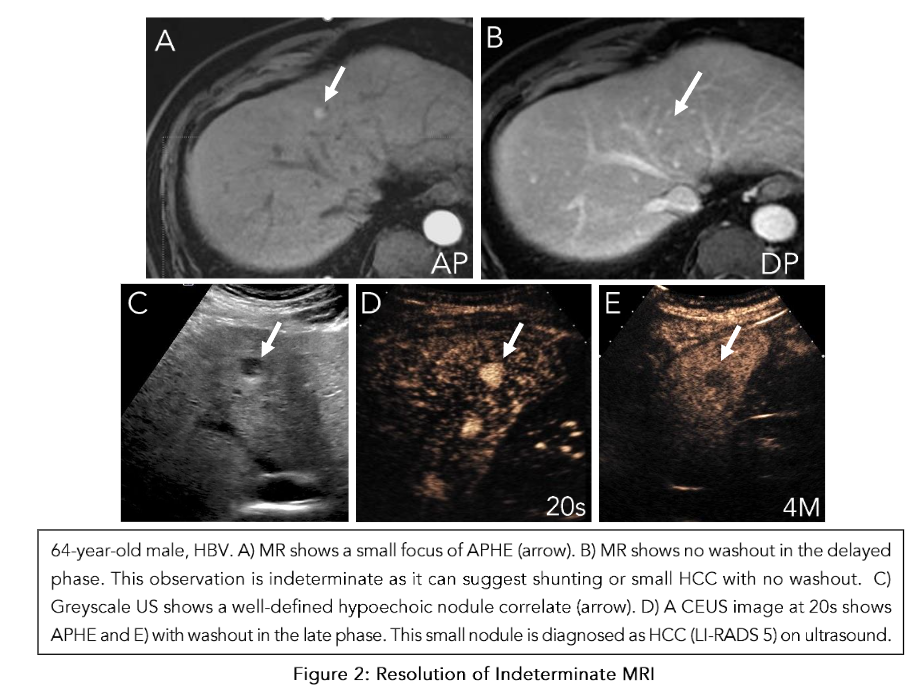

Additionally, care needs to be taken when interpreting APHE on CT and MRI in cirrhotic livers because they may represent pseudolesions such as nontumorous arterioportal shunts (Figure 2). These pseudolesions can be evaluated with US as a problem-solving tool to determine the presence of a true nodule and then characterize its enhancement and washout pattern.

Our validated provincial protocol uses CEUS as the first test to characterize focal liver lesions, with many not requiring MRI prior to management planning. In a prospective study of 195 at-risk patients receiving routine surveillance with greyscale US, CEUS LI-RADS categorization demonstrated equal if not superior efficacy to MRI in diagnosing HCC when used as a first-line test following positive surveillance ultrasound. Moreover, when we maintain ultrasound as the foundational imaging mechanism for both surveillance and nodule characterization, we can achieve better correlation of surveillance findings with CEUS than MRI. When it concerns sub-centimeter nodules flagged on surveillance for further characterization, CEUS also excels in characterizing the enhancement and washout properties given its high spatial resolution and purely intravascular contrast agent. In the event a sub-centimeter nodule demonstrates APHE and late and weak washout, it is categorized as LI-RADS 4, but individual discretion dictates whether a short interval follow-up (less than 3 months) or immediate treatment is appropriate. CEUS also plays an important role when evaluating complications such as HCC rupture (Figure 7). Outside of following up positive surveillance findings, CEUS plays an important role in clarifying indeterminate findings on CT or MRI. In a prospective study of 27 indeterminate hepatic nodules characterized on CT, CEUS was able to accurately diagnose HCC in 7 cases. CEUS and MRI are also able to comparatively supplement each other in cases where there is no definitive diagnosis of HCC. Overall, a complementary framework where these imaging modalities are used in a multidisciplinary approach to HCC diagnosis is critical when forming management strategies.